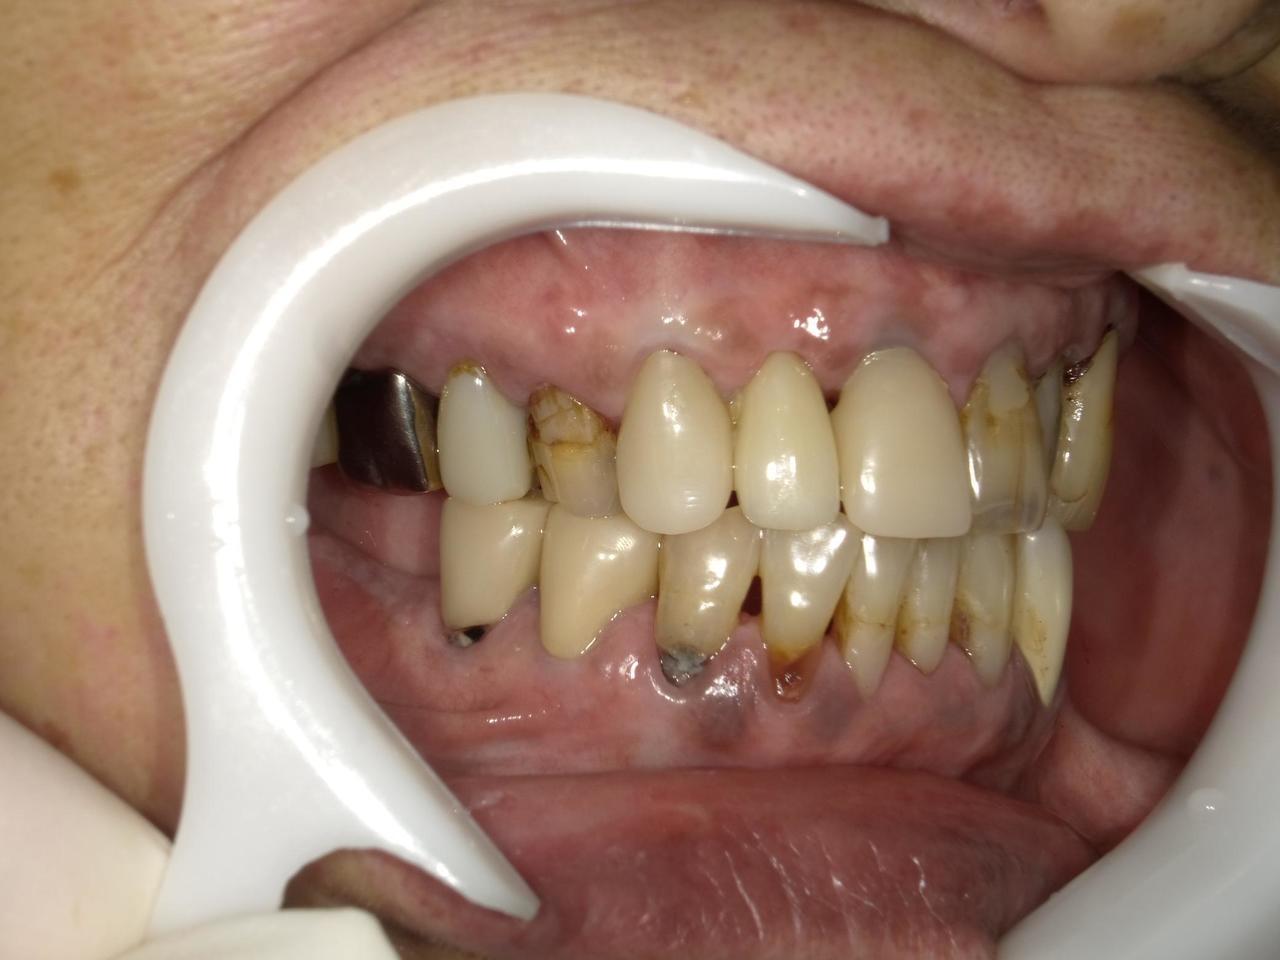

Before

枚方市のインプラントの症例

After

K・S様 女性 60代

症状としては、 右上4から7番までのすべての歯の著しい動揺があり、食事が困難であった。

治療法としては、患者様は、患者様が3か月以内の治療完了を望んでいたために、炎症が若干あったが、右上4から7番ぼすべての抜歯を行い、右上4番(抜歯即時埋入)、右上6番(上顎洞までの骨がほとんどないため、グラフトレスサイナスリフト施行)にインプラントを1回法で手術を終え、2か月半後にインプラントの状態が安定したために、3か月で上部構造の、右上456のジルコニアブリッジを装着して、治療を終えています。

治療結果としては、抜歯したと同時にインプラントを埋入することで、抜歯した穴が自然に治る過程で、インプラントの骨結合と組織の治癒が同時に行われるために、3か月という治療期間で治療を終了することができたことと、機能面・審美面でも回復を行うができた。また、右上6番に関しては、グラフトレスサイナスリフトを行うことで、従来のサイナスリフトに比べ、約9か月早く治療を終えることができました。

治療の期間・回数:約3か月、インプラント抜歯即時埋入から最終補綴物装着まで8回

治療の価格:792000円(税込)

治療費の内訳:インプラント基本料(フィックスチャー(メガジェンインプラントANYONE使用) 及び手術費用、投薬費用、レントゲン費用、インプラント上部費用(アバットメントおよびジルコニアクラウンの費用用)330000円×2 660000円(税込み)。オプション、抜歯即時埋入加算(人工骨費用を含まず)5500円×2 11000円(税込み)右上5ジル9コニアブリッジのポンテック費用 88000円 右上6グラフトレスサイナスリフト費用 33000円(税込み

治療のリスクや副作用:手術後に、痛みや腫れ、出血、合併症などを引き起こす可能性があります。噛む感覚がご自身の歯と異なる場合があります。見た目がご自身の歯と異なる場合があります。手術後にメインテナンスを継続しないと、インプラントが抜け落ちる可能性があります。